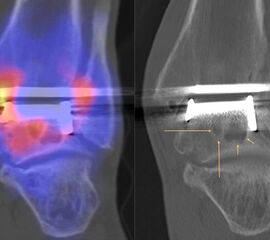

Beispiele für SPECT/CT-Untersuchungen nach OSG-TEP sind in den Abbildungen 6.1. bis 6.3. abgebildet.

Zur Zuordnung von Mehrspeicherungen und morphologischen Veränderungen im Bereich von Prothesen eignen sich folgende Kriterien 51:

• Flächiger starker Fokus am Prothesen-Knochen-Interface → V. a. Lockerung

• Fokus medial oder lateral am Prothesen-Knochen-Interface → V. a. fokaler biomechanischer Stress aufgrund von Fehlstellung der Prothese oder des Rückfußes

• Fokus medial oder lateral im Gelenkabschnitt / Zone zwischen Talus und den Malleolen → Ausdruck eines Impingement

• Im CT zart randsklerosierte rundliche Osteolyse(n) am Prothesen-Knochen-Interface mit metabolischem Fokus → V. a. symptomatische Zyste

• Fokale oder flächige Mehranreicherungen in angrenzenden Gelenken in Verbindung mit arthrotischen Veränderungen im CT → V. a. symptomatische Arthrose

Gurbani et al. evaluierten 37 Patienten mit schmerzhaften Sprunggelenkprothesen mit SPECT/CT und korrelierten die Ergebnisse mit klinischen und intraoperativen Befunden. Die SPECT/CT-Ergebnisse korrelierten zu 89,2 % (33/37 Pat.) mit der definitiven Diagnose. 28 Patienten wurden operativ revidiert und der Vergleich der SPECT/CT-Befunde mit den intraoperativen ergab eine Übereinstimmung von 92,9 % (26/28 Pat.). Die SPECT/CT identifizierte in den meisten Fällen aseptische Lockerungen (12/33 Pat.) und Impingement (11/33 Pat.). Seltenere Diagnosen waren Fehlstellungen (4/33 Pat.), Zystenbildungen (2/33 Pat.), subtalare Arthrosen (2/33 Pat.) und Infektionen (2/33 Pat.) 51.